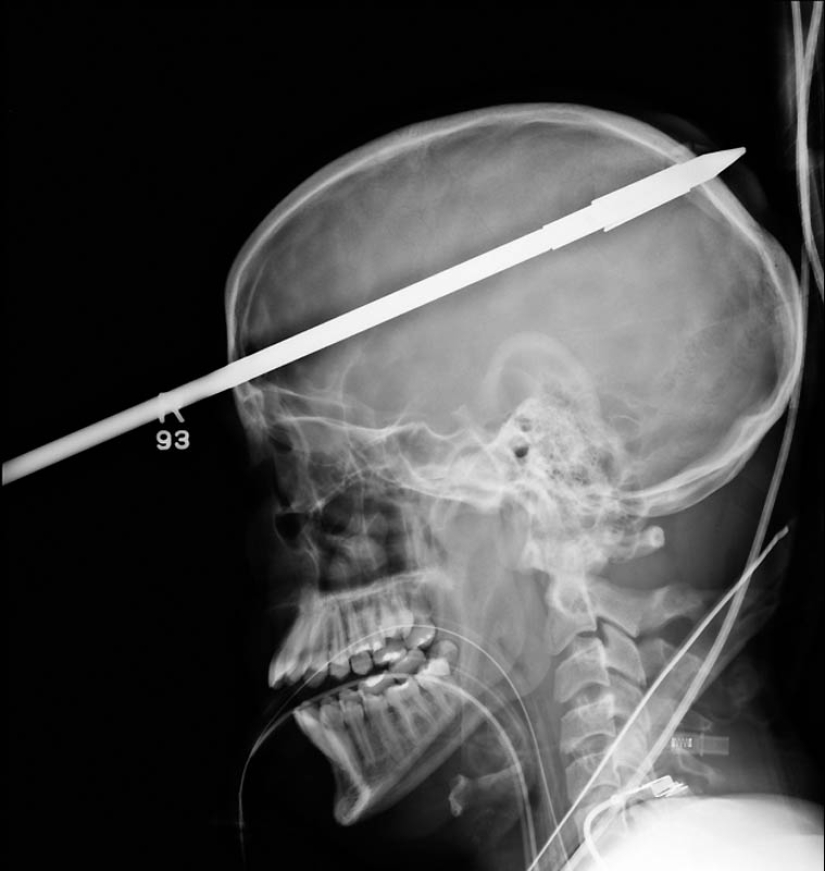

11. Una lanza de un arpón que golpeó a un niño de 16 años en la cabeza en un viaje de pesca.